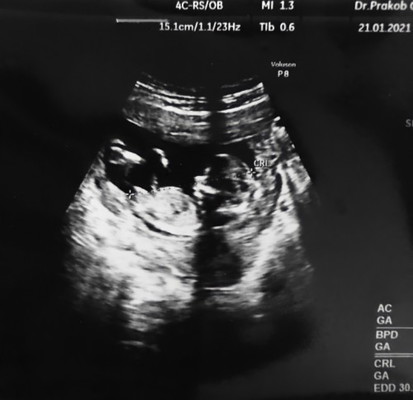

ตอนนี้ท้องได้13w อยากรู้เพศมาก แบบนี้พอเดากันออกมั้ยคะว่าเพศอะไรเดาเล่นๆค่ะ ส่วนมากแม่ๆรู้เพศเร็วสุดกี่วีคคะ